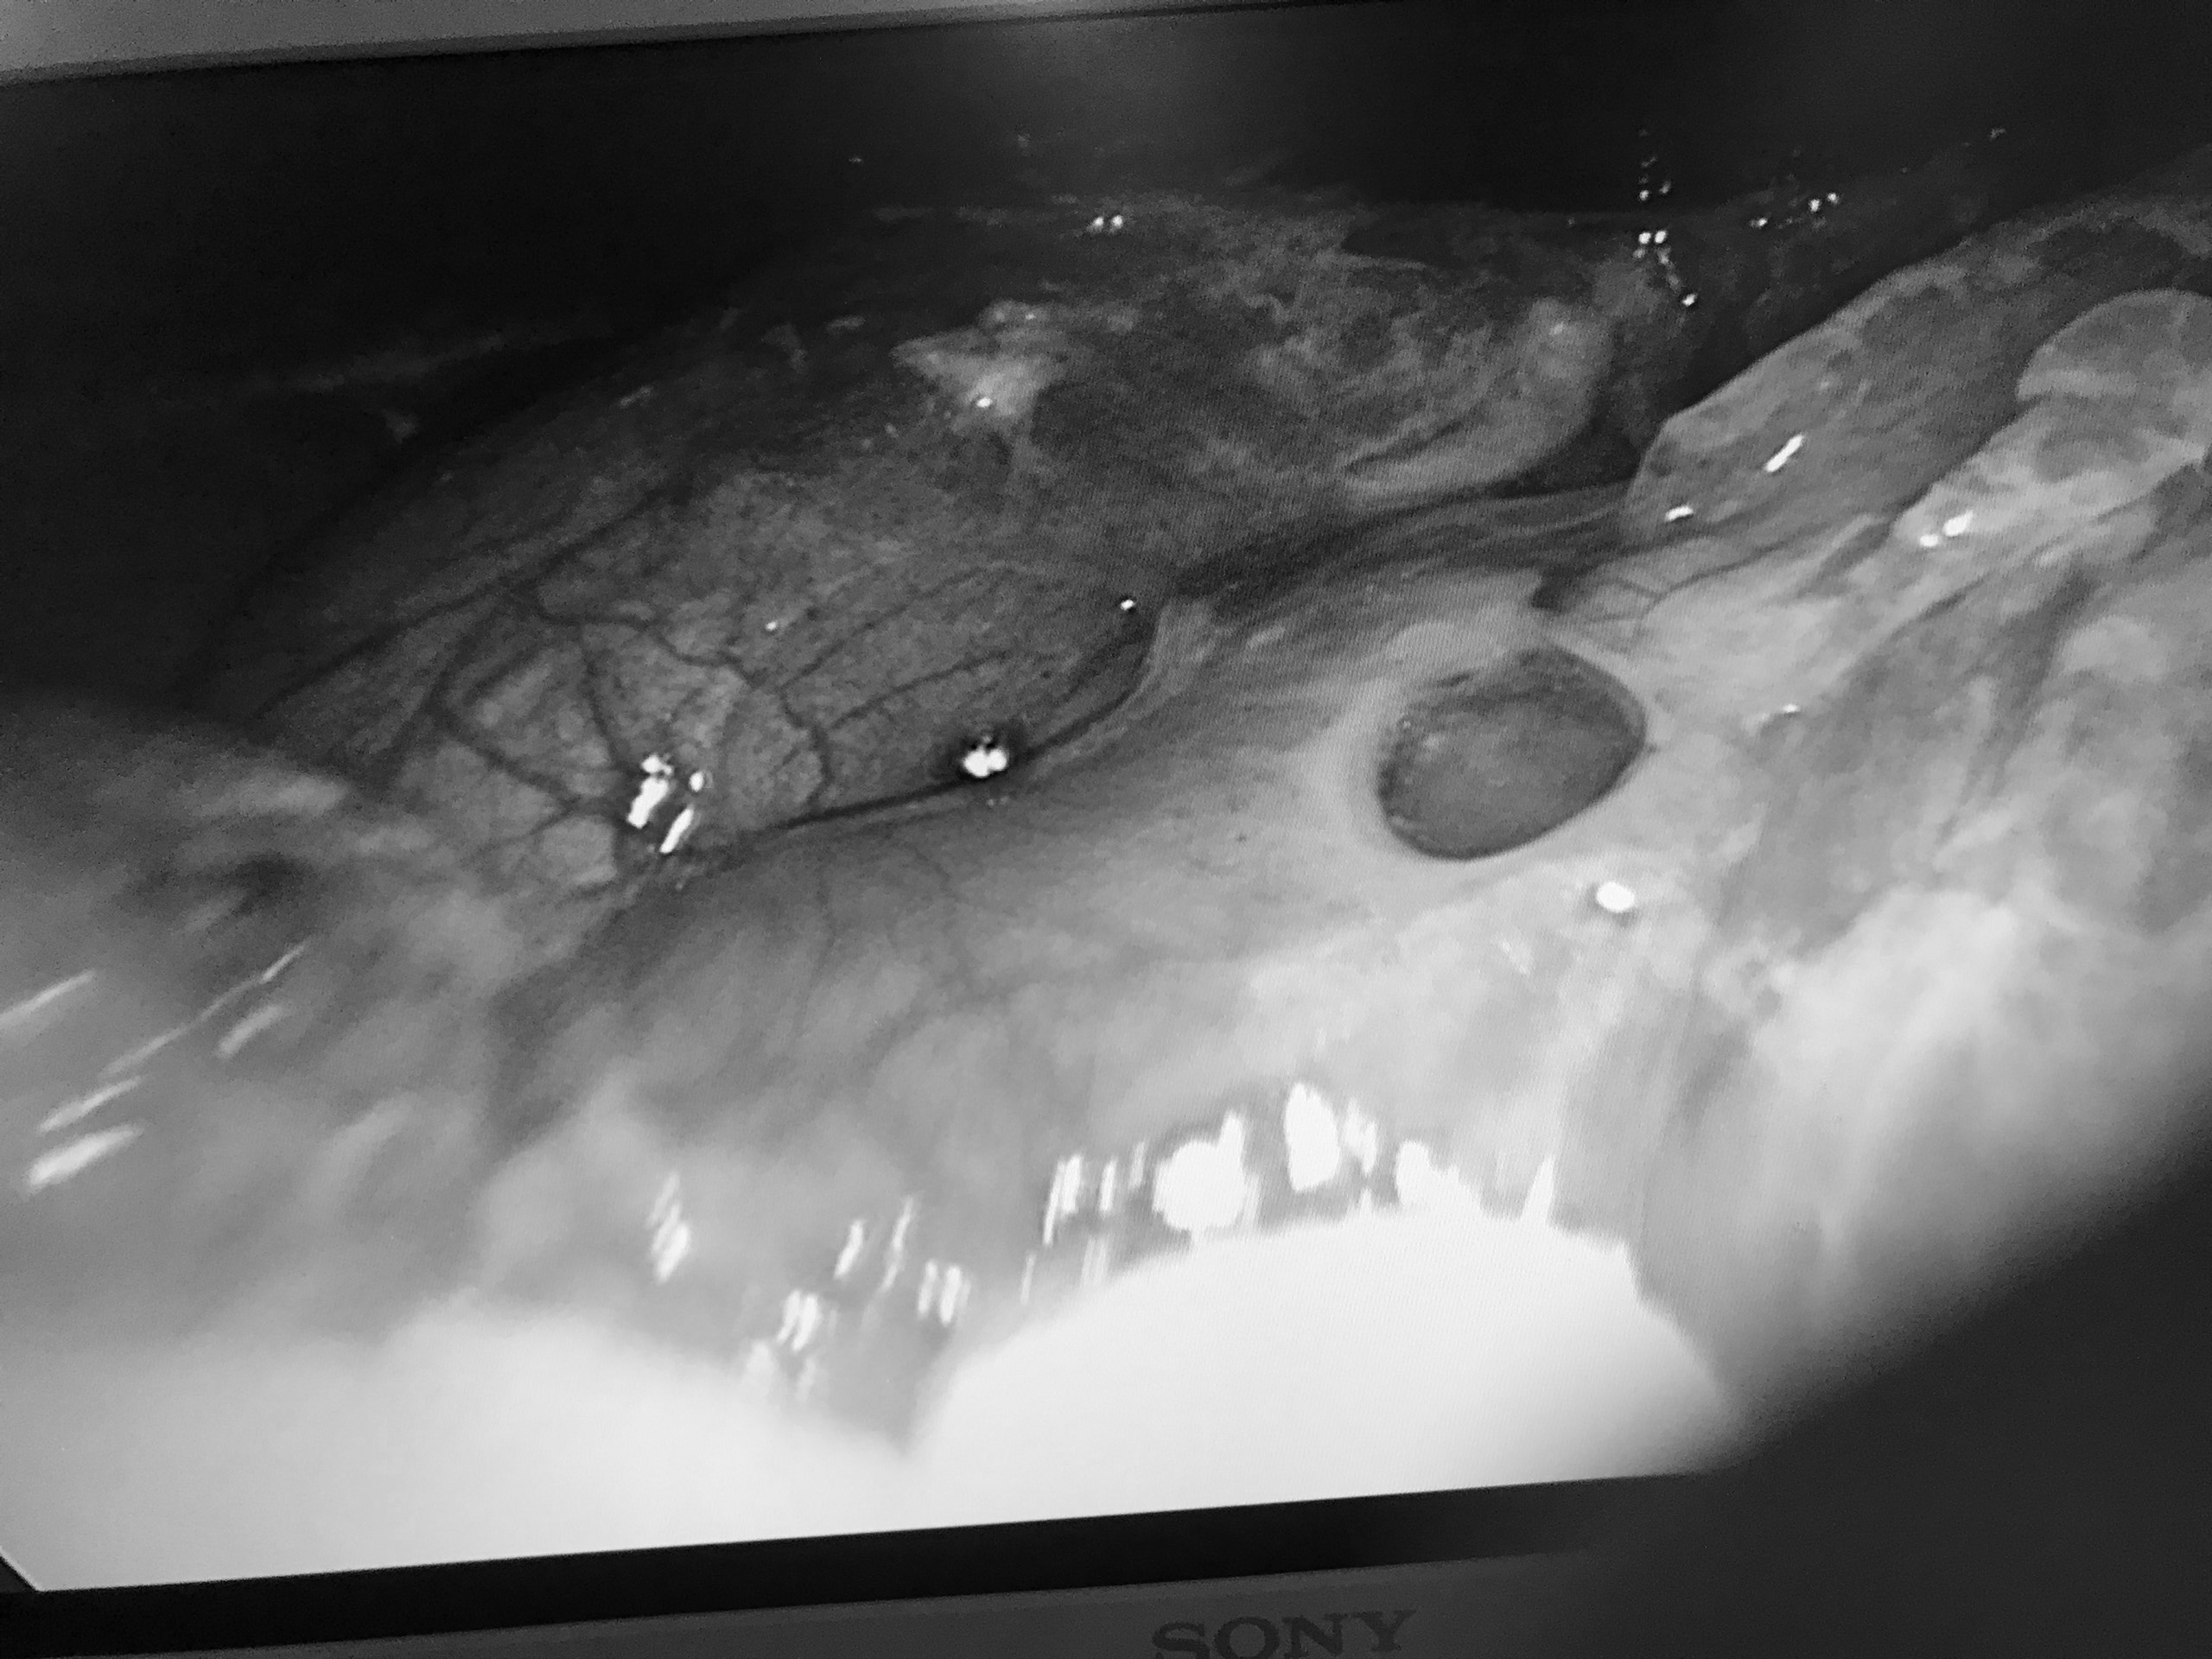

Bệnh nhân bị thủng dạ dày sau thời gian dài sử dụng thuốc nam. Ảnh: BVCC.

Tại trung tâm y tế, người bệnh được phẫu thuật cấp cứu, mổ nội soi bơm rửa sạch ổ bụng, khâu lỗ thủng tá tràng, dẫn lưu ổ bụng.